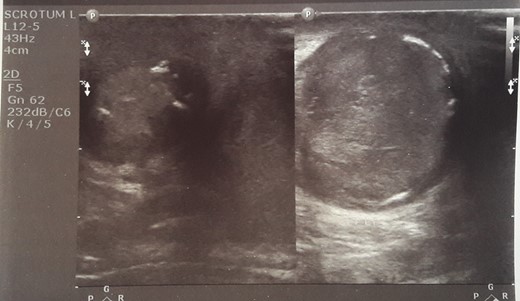

Initial sonographic findings were suggestive of epididymo-orchitis. The testis was well perfused and in normal position (Fig. 1). He was admitted for 3 days to start intravenous anti-inflammatory and antibiotic treatment and discharged under antibiotic treatment. Re-examinations were scheduled to assess treatment. On first reexamination, a week later, edema had subsided and the testis appeared hard, indurated and painless (Fig. 2). Ultrasound was still suggestive of epididymo-orchitis. Nevertheless suspicion for a testicular tumor was raised because of persistence of clinical and sonographic findings. An earlier appointment was scheduled this time. Five days later, at the second reexamination, another ultrasound showed reduced testicular perfusion that reached only the periphery of the testicular parenchyma (Fig. 3). The boy was operated as an emergency. Intraoperatively testis was non-twisted, with normal vas and vessels that ended in a necrotic testicular parenchyma. The testis was dark brown, hard on palpation and no blood came out when incised (Fig. 4). Right orchidectomy was performed. Since the exact cause of testicular necrosis was still unkown at the time of operation a left orchidopexy was performed to protect the only surviving testis from any future risk of torsion. The boy was discharged the next day. Histology showed a case of epididymitis nodosa and ruptured sperm granuloma that caused vascular compression, thrombosis and testicular necrosis (Fig. 5). More specifically, it showed proliferation of small ducts and gland-like structures in the walls of the vas deferens and epididymis in response to fluid and sperm dissection into the interstitium secondary to mechanical obstruction and increased intraluminal pressure. These findings are extremely rare in pediatric patients. The boy had an uneventful postoperative course and was discharged 2 days after surgery able to travel by sea to his home island.

Initial sonographic findings were suggestive of orheoepididymitis.

On re-examination a week later, edema had subsided and the testis appeared hard, indurated and painless.

Five days later another ultrasound showed reduced testicular perfusion that reached only the periphery of the testicular parenchyma.